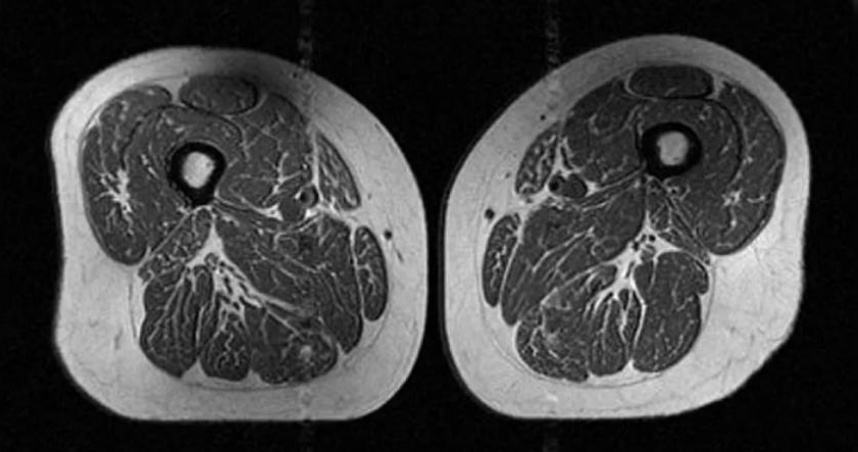

大腿肌肉

脂肪浸潤

A5和牛

肌肉品質